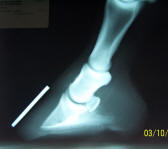

May '04

14 degree rotation, P3 penetrating the soles on both front

feet. |

Dec '05

It can be done! I don't mean survive, I mean perform!!! |

This owner stood

up to countless people telling her this horse couldn't be

helped. Horse and rider have dominated in competition this

year. The "after" picture was taken on the day this horse

was awarded the Speed Event Championship Buckle for the year

in our local saddle club. |